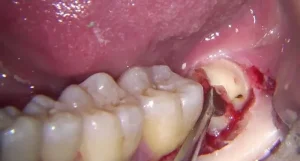

Periodontal disease, also known as gum disease, is a common dental problem that can lead to serious complications if not treated properly. It affects the